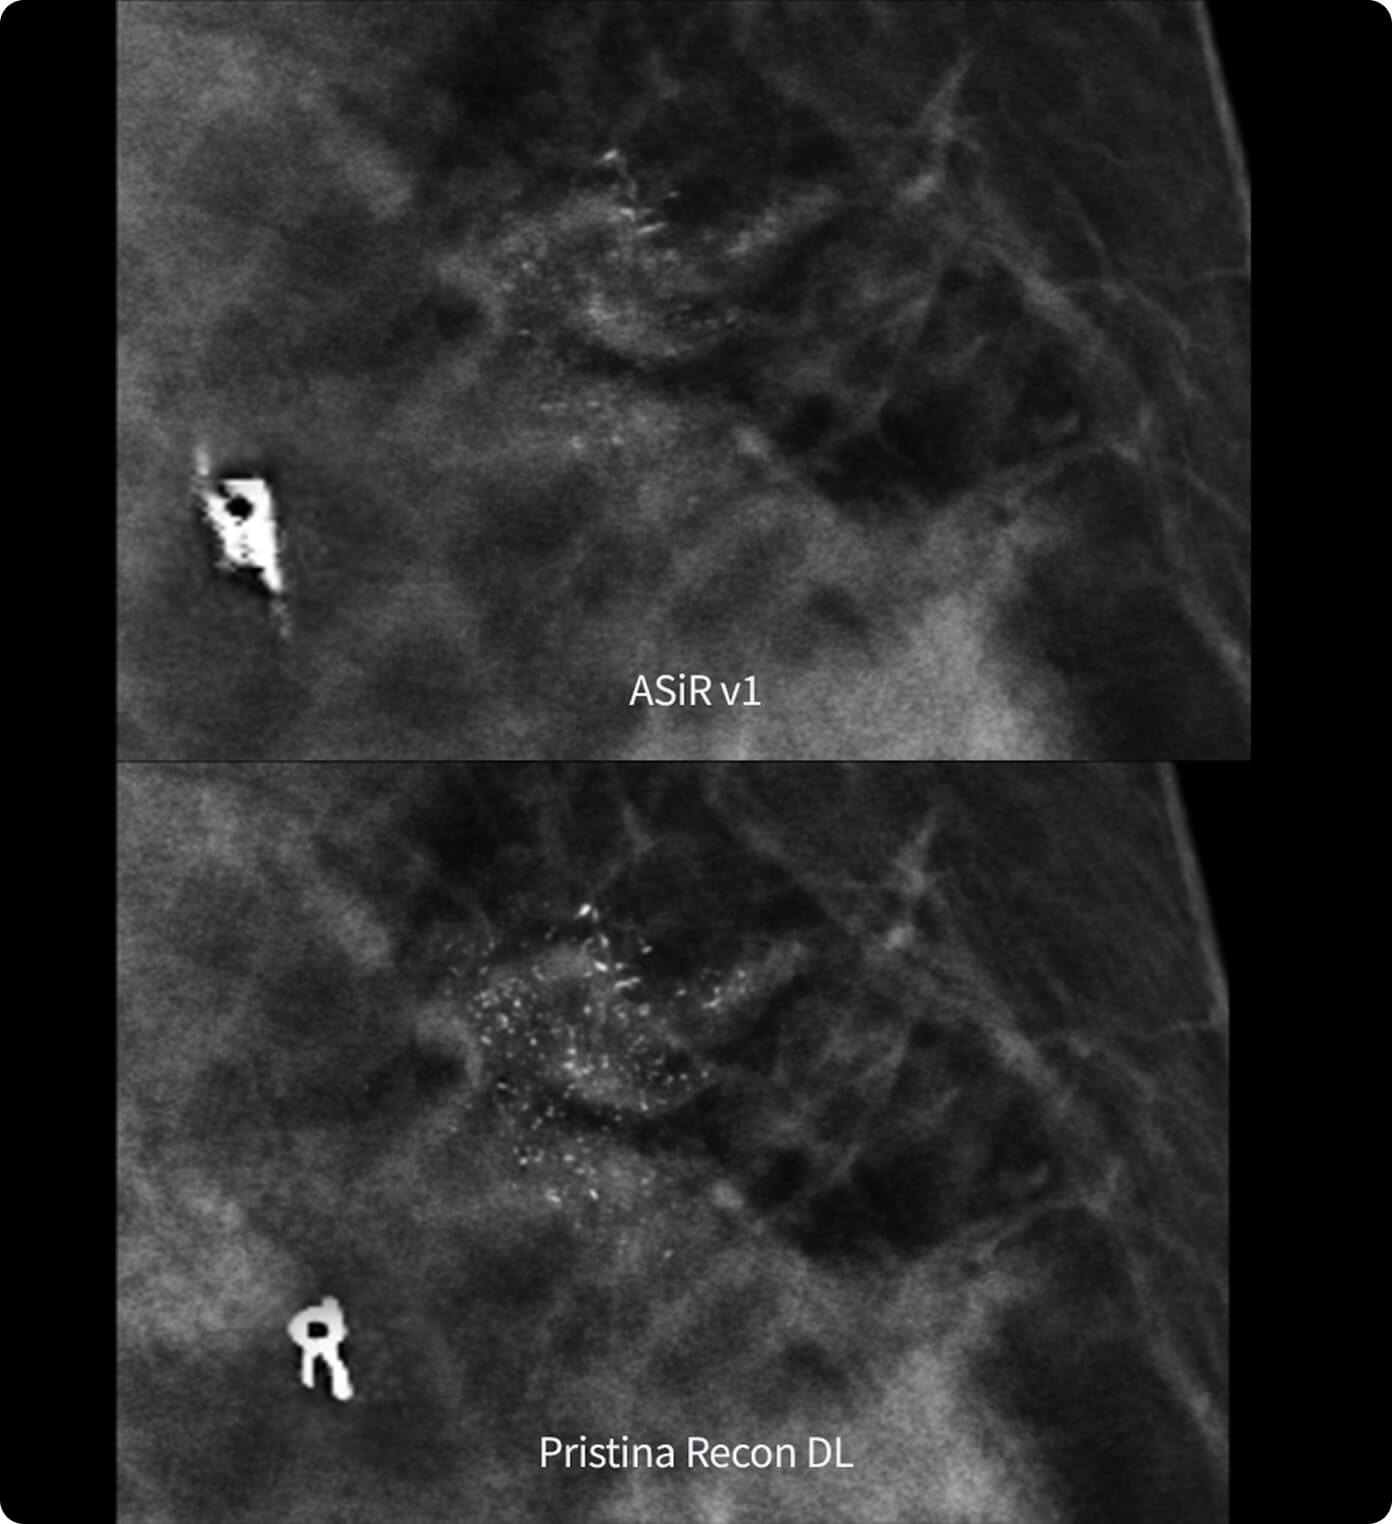

Alimentado por la tecnología SignalMax™, para que no tenga que comprometer la calidad de la imagen para la portabilidad